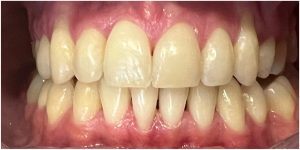

Dzięki precyzyjnej diagnostyce, doktor Magdalena Zawirska opracowała kompleksowy plan leczenia, który obejmował: stomatologię zachowawczą, periodontologię i protetykę stomatologiczną. Zastosowano licówki i korony pełnoceramiczne, przeprowadzając kompleksową rekonstrukcję zwarcia.

Pacjentka może się teraz cieszyć się pięknym i zdrowym uśmiechem